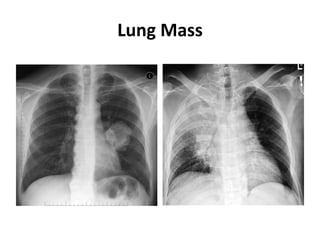

Lung Mass